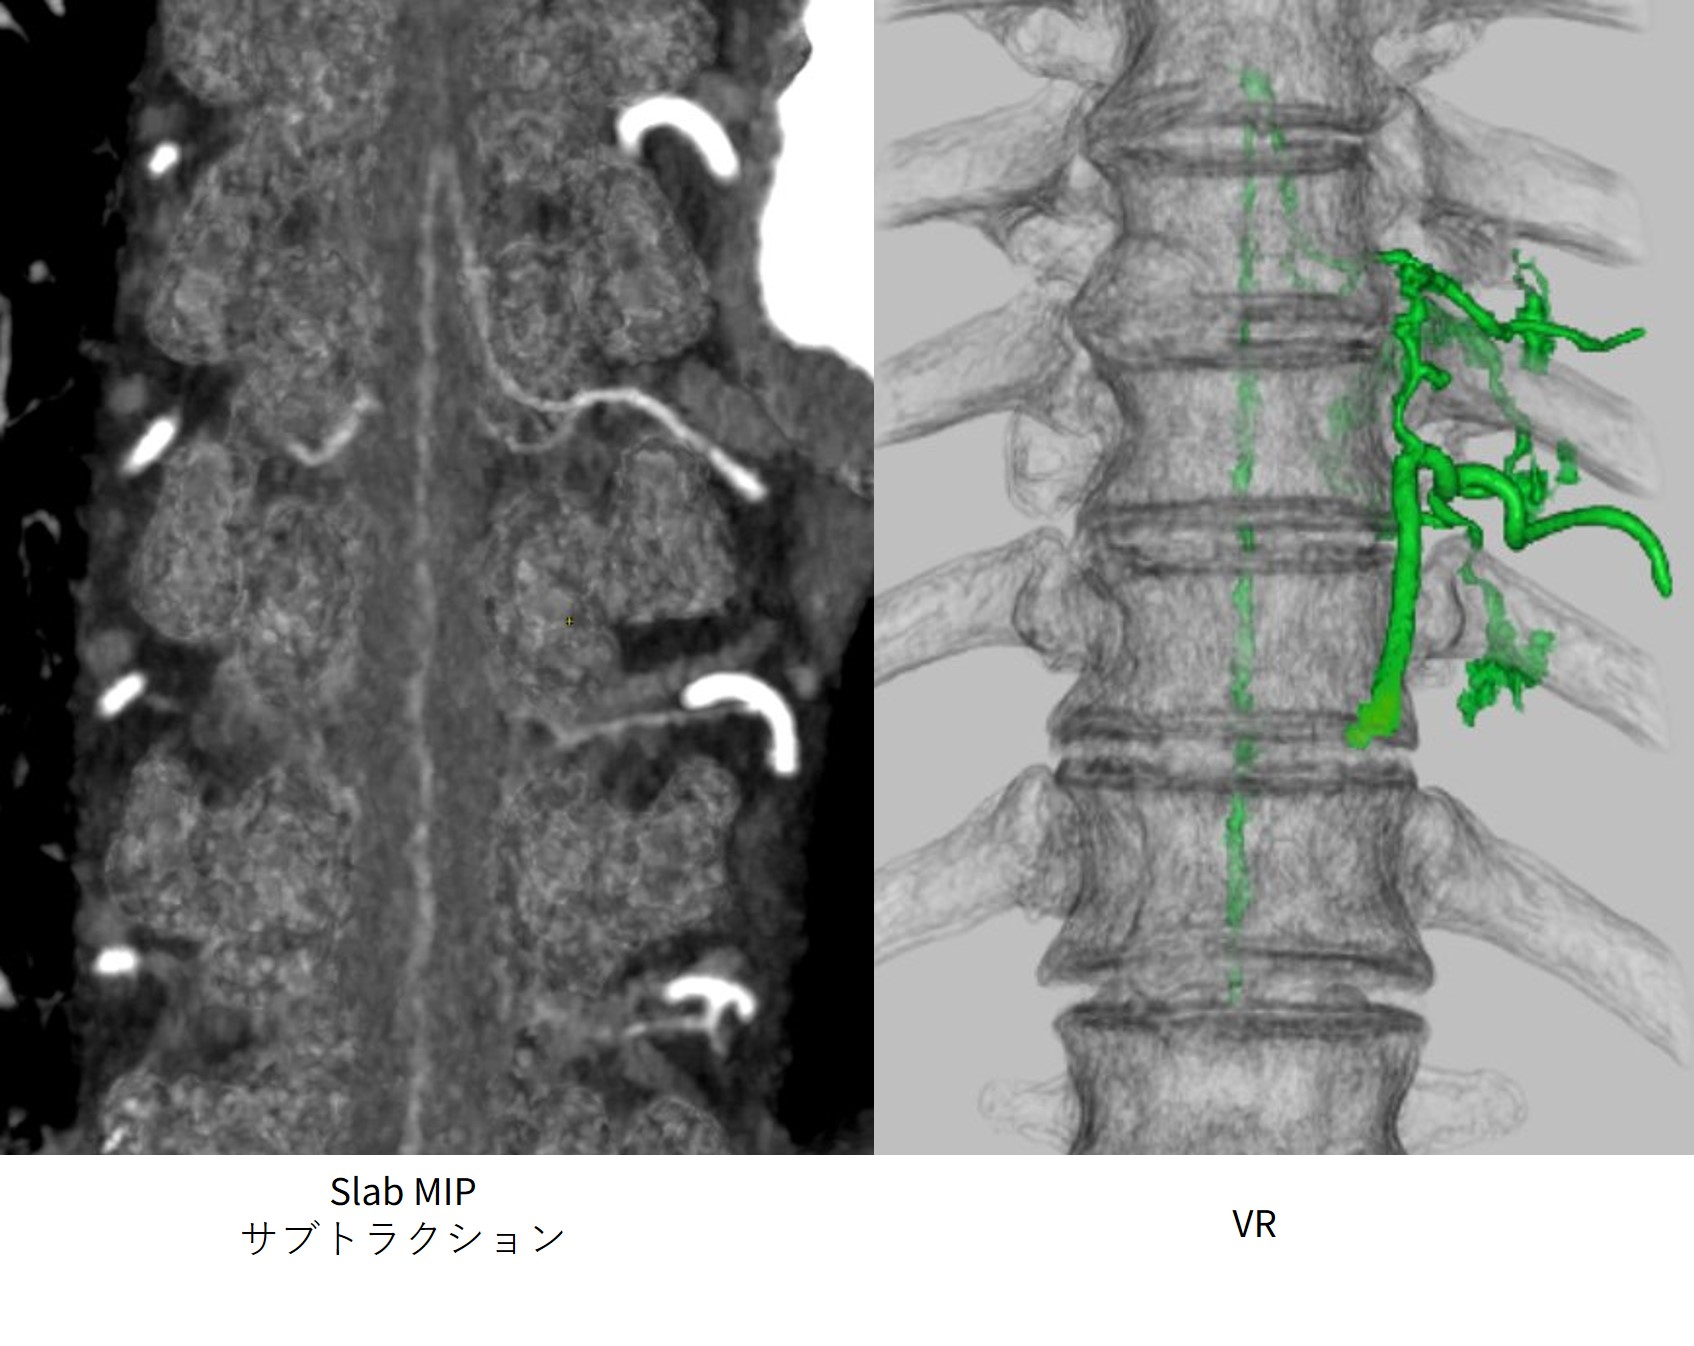

症例4)アダムキュービッツ動脈

TEVARを予定しており、動脈瘤のフォローおよびアダムキュービッツ動脈の同定目的のために検査実施。アダムキュービッツ動脈は細く描出が困難のため、造影効果を上げる目的で、DEを用いて撮影。造影条件は28mgI/kg/sec・28秒注入。横隔膜レベルでPrep開始しCT値200でトリガーをかけ、10秒後に15秒撮影をした。造影効果を上げるため50keVで再構成を行い、単純も造影と同様50keVで再構成しサブトラクションをおこなった。アダムキュービッツ動脈は左第9肋間動脈からの分岐している(Fig.6)。

revolutionapexelite_aomori10.jpg

Fig.6 DEにより画像化できたアダムキュービッツ症例